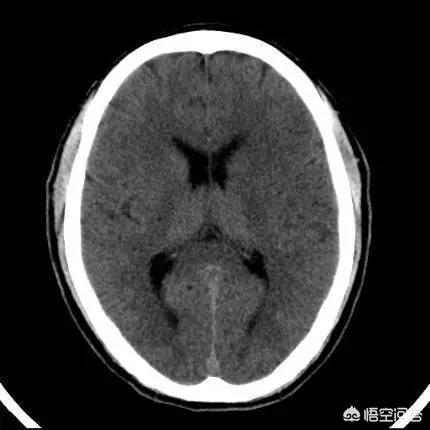

Après avoir été envoyé à l'hôpital, la clinique d'urgence a ouvert un canal vert pour que M. Xu effectue un examen tomodensitométrique de la tête, sans foyer de saignement, avec une tension artérielle de 170/92 mmHg, un ECG suggérant un "rythme sinusal, une onde Q anormale dans la veine ventriculaire, un infarctus du myocarde au niveau de la paroi inférieure (moment à déterminer)", et vérifiant en même temps les analyses sanguines courantes, la troponine, la fonction de coagulation et les enzymes cardiaques. Aucune anomalie n'a été constatée. Par la suite, l'ARM a montré un infarctus lacunaire coronal radial droit, et le score NIHSS était de 5. Il a été admis en urgence dans le service de neurologie pour un "infarctus cérébral aigu".

ii,Certains patients atteints d'infarctus cérébralParce que le site de l'infarctus ne se trouve pas dans la zone fonctionnelle, ou que la zone de l'infarctus est petite, l'impact sur la fonction du patient est faible et n'apparaît pas ; ou certains patients n'ont même pas fait l'examen, la survenue d'un infarctus cérébral est également possible.inconscient. Par conséquent, certains patients présentent des lésions d'infarctus cérébral lorsqu'ils arrivent à l'hôpital peu de temps après le début de la maladie, ce qui est très probablement dû à des lésions antérieures. En effet, les nouveaux infarctus cérébraux ne sont apparents au scanner qu'environ 24 heures après le début de la maladie.

(Image tirée du site web)